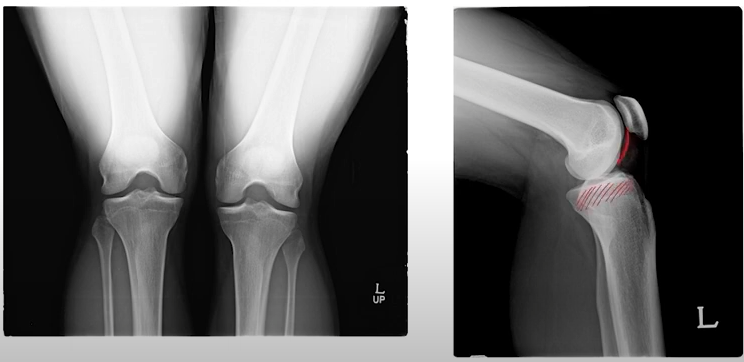

다른 관절들과 다르게 무릎의 관절은 엄청 큰 무게를 일정한 관절면에서 부담해야하기 때문에

다른 관절들보다 퇴행성 관절염이 진행하기 쉬운 관절입니다.

일자인 판 모양의 경골 위에 둥그런 대퇴골이 올려있다고 생각해보면 쉽습니다.